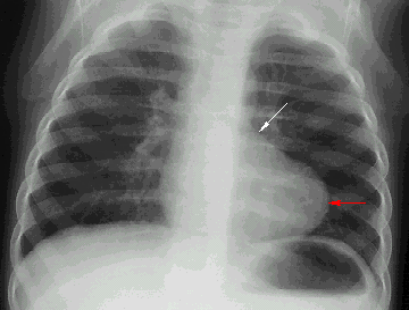

法洛四联症(靴形心)

新颖大小正常;心尖上翘(右室大);

肺动脉段凹陷

肺血少